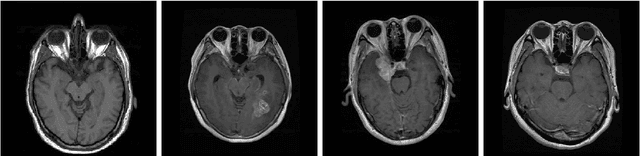

Abstract:Brain tumor detection and classification are critical tasks in medical image analysis, particularly in early-stage diagnosis, where accurate and timely detection can significantly improve treatment outcomes. In this study, we apply various statistical and machine learning models to detect and classify brain tumors using brain MRI images. We explore a variety of statistical models including linear, logistic, and Bayesian regressions, and the machine learning models including decision tree, random forest, single-layer perceptron, multi-layer perceptron, convolutional neural network (CNN), recurrent neural network, and long short-term memory. Our findings show that CNN outperforms other models, achieving the best performance. Additionally, we confirm that the CNN model can also work for multi-class classification, distinguishing between four categories of brain MRI images such as normal, glioma, meningioma, and pituitary tumor images. This study demonstrates that machine learning approaches are suitable for brain tumor detection and classification, facilitating real-world medical applications in assisting radiologists with early and accurate diagnosis.